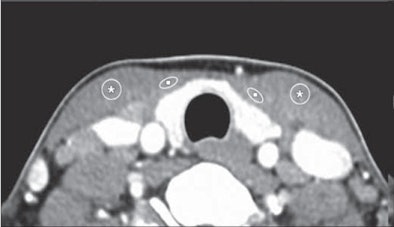

| Compared with unshielded CT image (above), mean attenuations of both superficial neck muscles (strap muscle [squares] and sternocleidomastoid [asterisks]) are higher in shielded image (below), whereas image noises do not show significant difference. Images republished with permission of the American Roentgen Ray Society from AJR 2011; Vol. 196:3, pp. 611-615. |

Lee and his team looked at two groups of patients who were imaged with neck CT but ultimately shown to be without abnormalities. One group had shielding and the other did not. The shields were fabricated from a double layer of bismuth-impregnated latex placed with a 2-cm radiolucent cotton spacer to decrease streak artifacts near the contact surface with the shield. There were no significant demographic differences between the two groups.

The investigators measured CT attenuation and noise in the strap and sternocleidomastoid (SCM) muscles, as well as superficial radiation dose, using a head CT dose phantom containing ionization chambers located at the 3, 6, 9, and 12 o'clock positions.

The results showed that CT attenuation rose with use of the commercial bismuth shield.

"These differences between the shielded and unshielded neck CT examinations were statistically significant (p < 0.01), which implies that the use of the shield resulted in increased CT attenuation of the superficial neck muscles compared with the unshielded CT examination," the authors wrote.

At the same time, noise was unaffected by the use of shielding.

"These differences in noises measured in the superficial neck muscles between shielded and unshielded CT examinations were not statistically significant (p = 0.201 and p = 0.953, respectively)," the study team reported.

However, the shield also produced increased CT attenuation near the shield during neck CT examinations, while image noise was maintained.

"Our results with neck CT image assessment showed that CT attenuation values were inevitably increased in superficial anterior neck muscles below the shielded surface, although a 2-cm cotton spacer successfully prevented an increase in noise associated with shield application," they added.